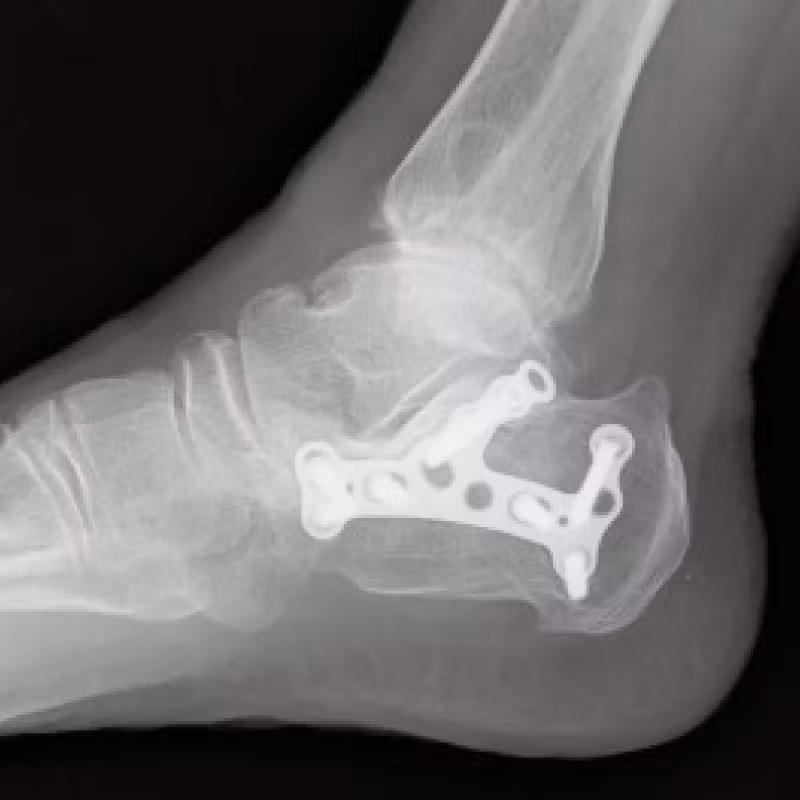

[踵骨骨折 骨接合術]